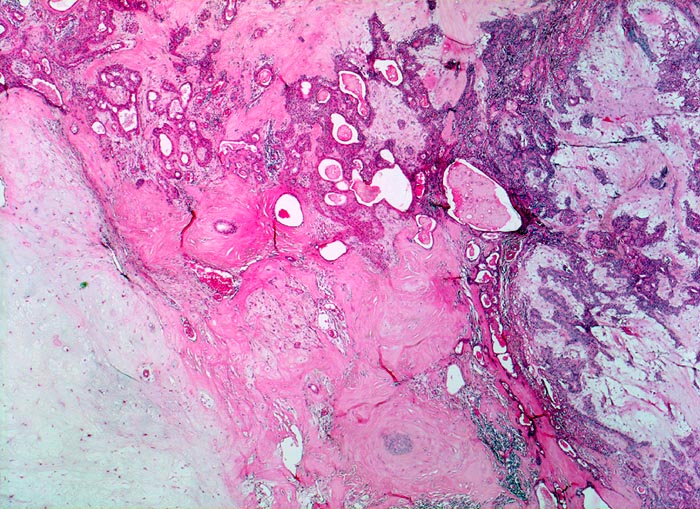

Die architektonischen und zytologischen Befunde sind äusserst variabel. Pleomorphe Adenome bestehen aus einer duktalen epithelialen, einer myoepithelialen und einer mesenchymalen Komponente mit myxoider, hyaliner, chondroider oder ossärer Differenzierung. Der Prozentuale Anteil der verschiedenen Komponenten ist von Tumor zu Tumor sehr unterschiedlich. Gangstrukturen werden von einem einreihigen duktalen Epithel ausgekleidet. Das Gangepithel kann eine Plattenepithelmetaplasie mit Verhornung zeigen. Die Myoepithelzellen umgeben die epithelial ausgekleideten Gangstrukturen, bilden Nester, solide Zellplatten, Trabekel oder liegen einzeln im mesenchymalen Stroma. Die Morphologie der Myoepithelien ist sehr variabel (spindelig, plasmazytoid, epitheloid, sternförmig oder basaloid).

• Scharf begrenzter bekapselter Tumor bestehend aus epithelialen, myoepithelialen und mesenchymalen Anteilen.

• Das Epithel bildet duktale Strukturen, welche von reichlich Myoepithelien umgeben werden.

• Epitheiale Gänge werden ausgekleidet von kubischen luminalen Zellen und einer oder mehreren äusseren Schichten myoepithelialer Zellen.

• In den stromareichen Arealen rechts finden sich plasmazytoide Myoepithelzellen mit reichlich eosinophilem Zytoplasma und einem exzentrisch gelegenen runden Kern.

• Die stromale Komponente ist teils mukoid, teils hyalinknorplig, teils hyalinisiert bindegewebig.